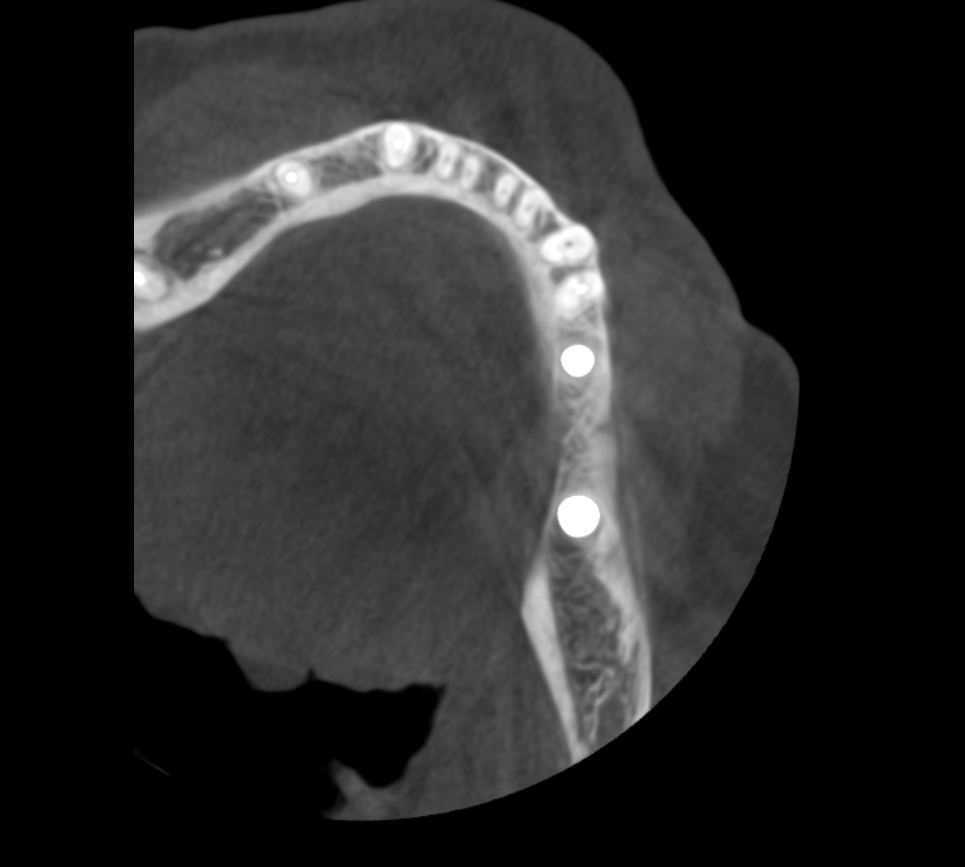

Теперь возьмём клинический случай (нижняя челюсть, отсутствия 35, 36, 37 зубов, атрофия альвеолярного гребня по ширине):

Но, насколько долговечен подобный результат остеопластики? Посмотрим на КЛКТ через 18 месяцев:

или

Как видите, даже структурно регенерат не отличается от подлежащего альвеолярного гребня, хотя заметен на снимке своей неестественной формой. Это говорит о том, что результат остеопластической операции стабилен, и мы можем быть спокойны за дальнейшую судьбу имплантов.